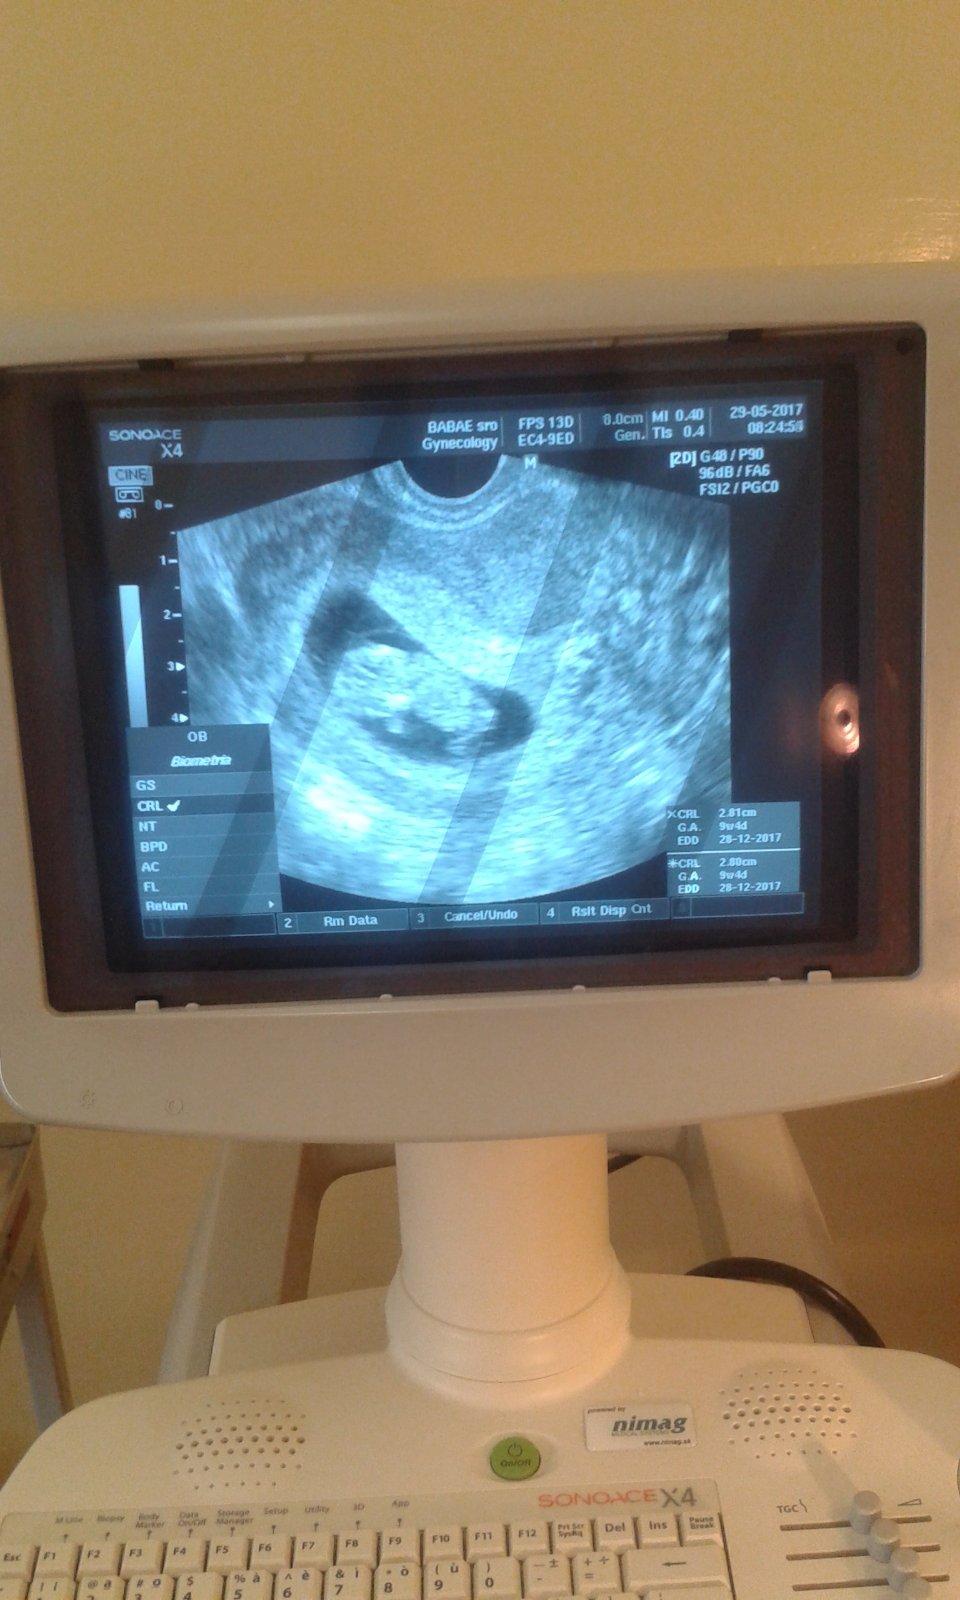

@kotatko12345 super blahozelam knizocku uz mas🙂ta dajak tie tyzdne nesedia fakt ved minule si bola 9plus4🙂

@archanjel007 buducu poradnu 9.6 uz dostanem.ved som sa ho pytala on ze tento tyzden je uz na 90% ale hlavne ze babo rastie povedal.

@kotatko12345 teraz by si mala byt 11 tyzden poslednykrat u lekara si bola 26.4 tam bolo babo velke na 6plus5 🙂

@kotatko12345 takze budeš rodiť okolo Silvestra som zvedavá ako mne ukáže najbližšie

@kotatko12345 bo aj poslednykrat si bola a bolo 9plus4 pred dvoma tyzdnami sice tam vravel ze je o dva tyzdne mensie no naj je vsetko ok hlavne